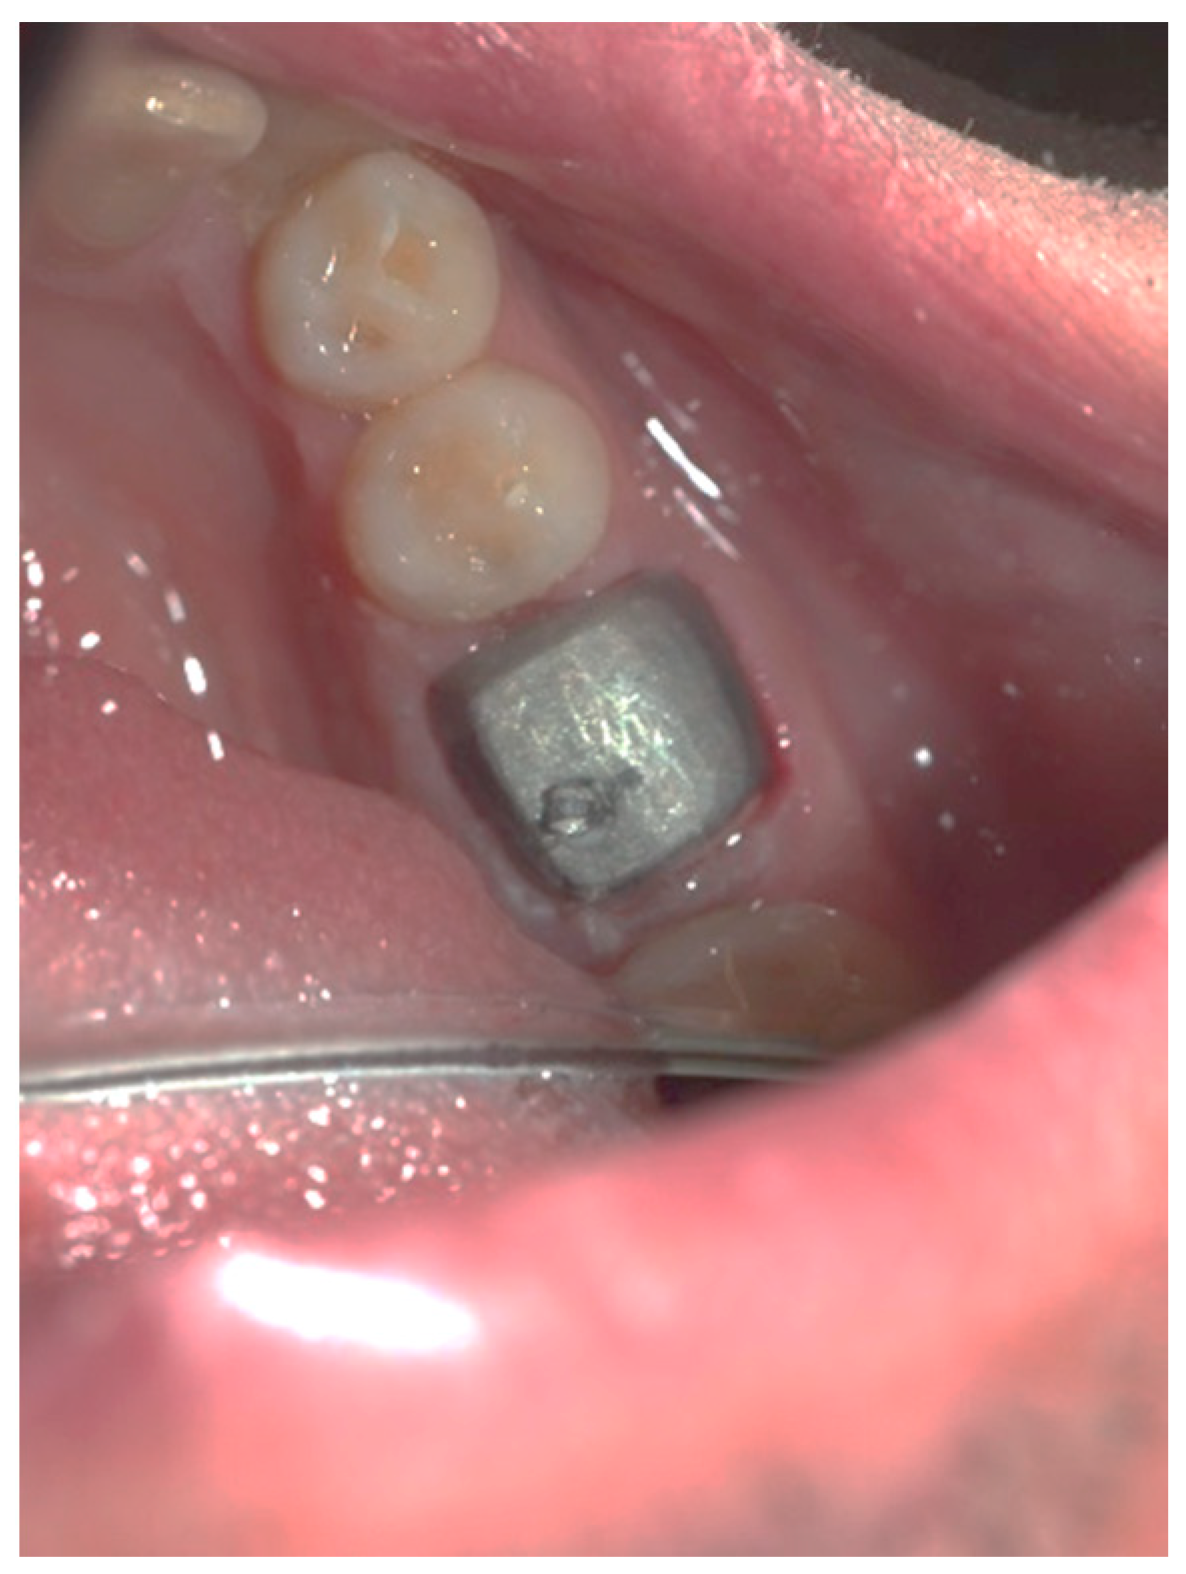

Figure 3, Figure 4, Figure 5, Figure 6, Figure 7 and Figure 8 display the follow-up of the healing process after a resective procedure for lengthening a short clinical crown with a laser.

Figure 4.

Healing at the 24th hour: the wound was covered with fibrinous plaque and an erythematous halo.

Figure 5.

Healing at the 72nd hour: the wound was covered with fibrinous plaque and an erythematous halo.